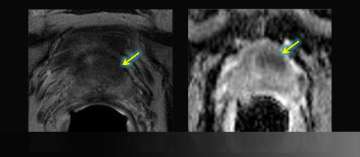

7) MR-Guided Targeted Biopsy

- 63 y/o, PSA 8.8 → 13.2 over 5 years

- All systematic biopsies negative

- Hypointense left anterior lesion with restricted diffusion is moderately suspicious, not in biopsy zone